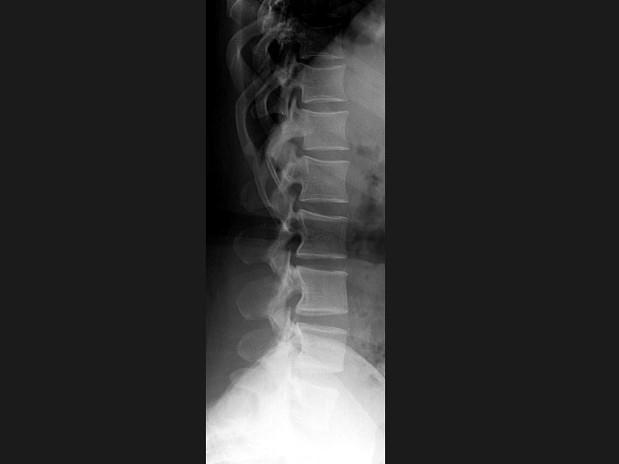

女,41岁,身材矮小,背痛,结合图像,最可能的诊断是?(?)A.腰椎退行性变B.腰椎间盘突出C.软骨发育不全D.石骨症E.马方综合征

问题 女,41岁,身材矮小,背痛,结合图像,最可能的诊断是?(?)

选项 A.腰椎退行性变 B.腰椎间盘突出 C.软骨发育不全 D.石骨症 E.马方综合征

答案 C